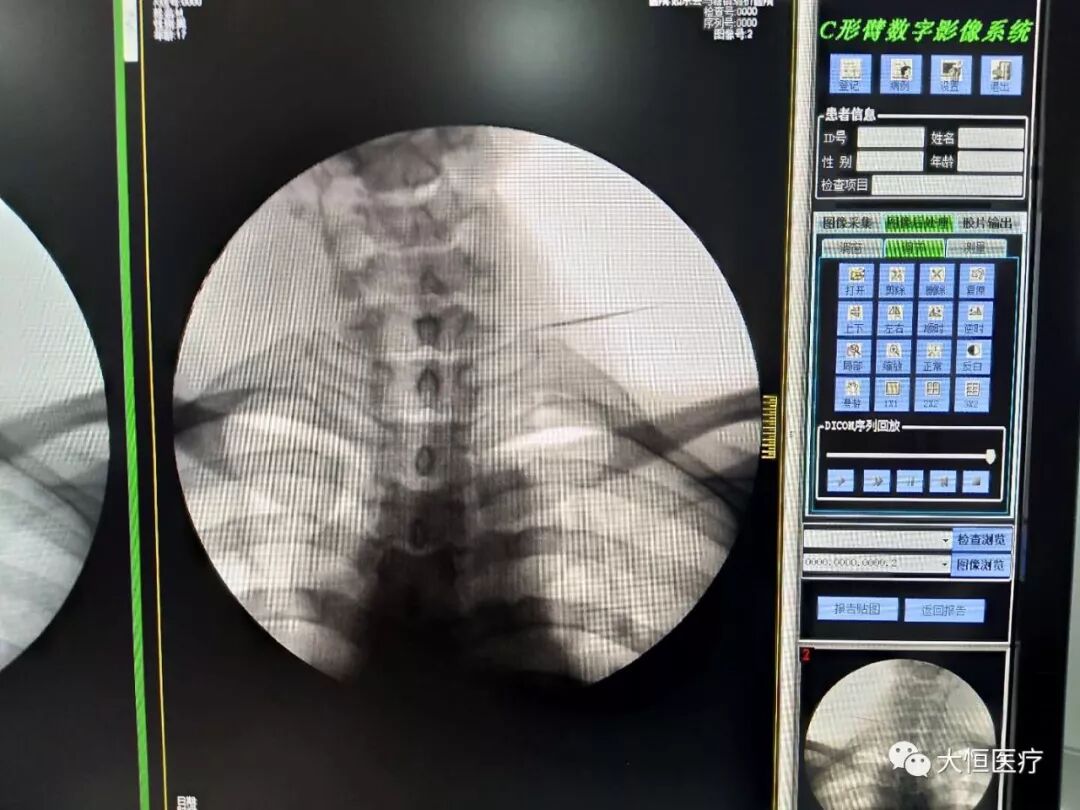

临床图像

c臂怎么启动全智能型疼痛科/介入型C型臂_https://www.jmylbn.com_新闻资讯_第2张